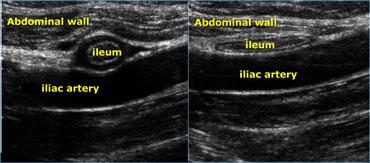

Siêu âm thời gian thực cho phép quan sát tác động của lực ép. So sánh hồi tràng bình thường đang co (trái) với hồi tràng giãn, xẹp ở cùng bệnh nhân vài giây sau (phải)

- Đặc điểm sau đặc biệt hữu ích để đánh giá xem các cơ quan hoặc mô có mềm mại hay cứng chắc hay không.

Siêu âm thời gian thực cho phép quan sát tác động của lực ép.

Ở ngoài cùng bên trái là hồi tràng bình thường đang co và bên cạnh là hồi tràng giãn, xẹp vài giây sau đó.